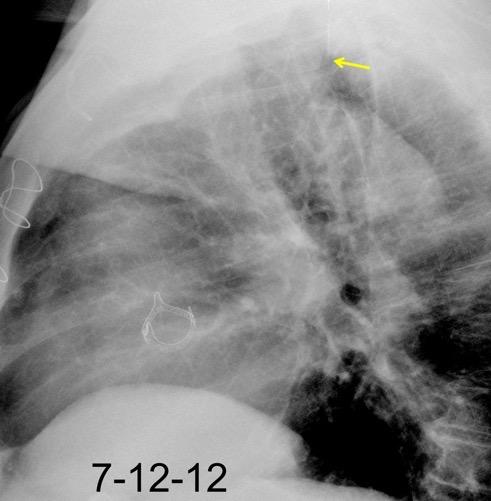

“Draped aorta”.

Indica rotura aórtica reciente. Se manifiesta por una pared aórtica posterior o el contacto con el borde lateral vertebral borrados por la hemorragia.

Rotura aneurisma de Aorta descendente.

Dolor. (10 días antes: "Rotura inminente”)